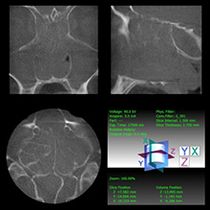

Zyste der linken Kieferhöhle (Digitale Volumentomographie, DVT)